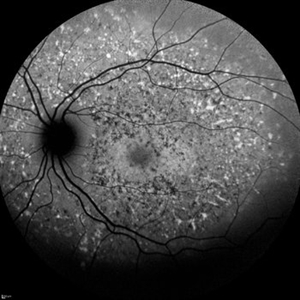

Cone-Rod Dystrophy

Dec 9 2021 by Filip Kecer

Fundus autofluorescence of a 12-year-old boy with genetically confirmed Cone-rod dystrophy.

Photographer: Filip Kecer

Imaging device: Spectralis, Heidelberg Engineering

Condition/keywords: autofluorescence imaging, cone dystrophy, dystrophy, rod dystrophy, Stargardt disease